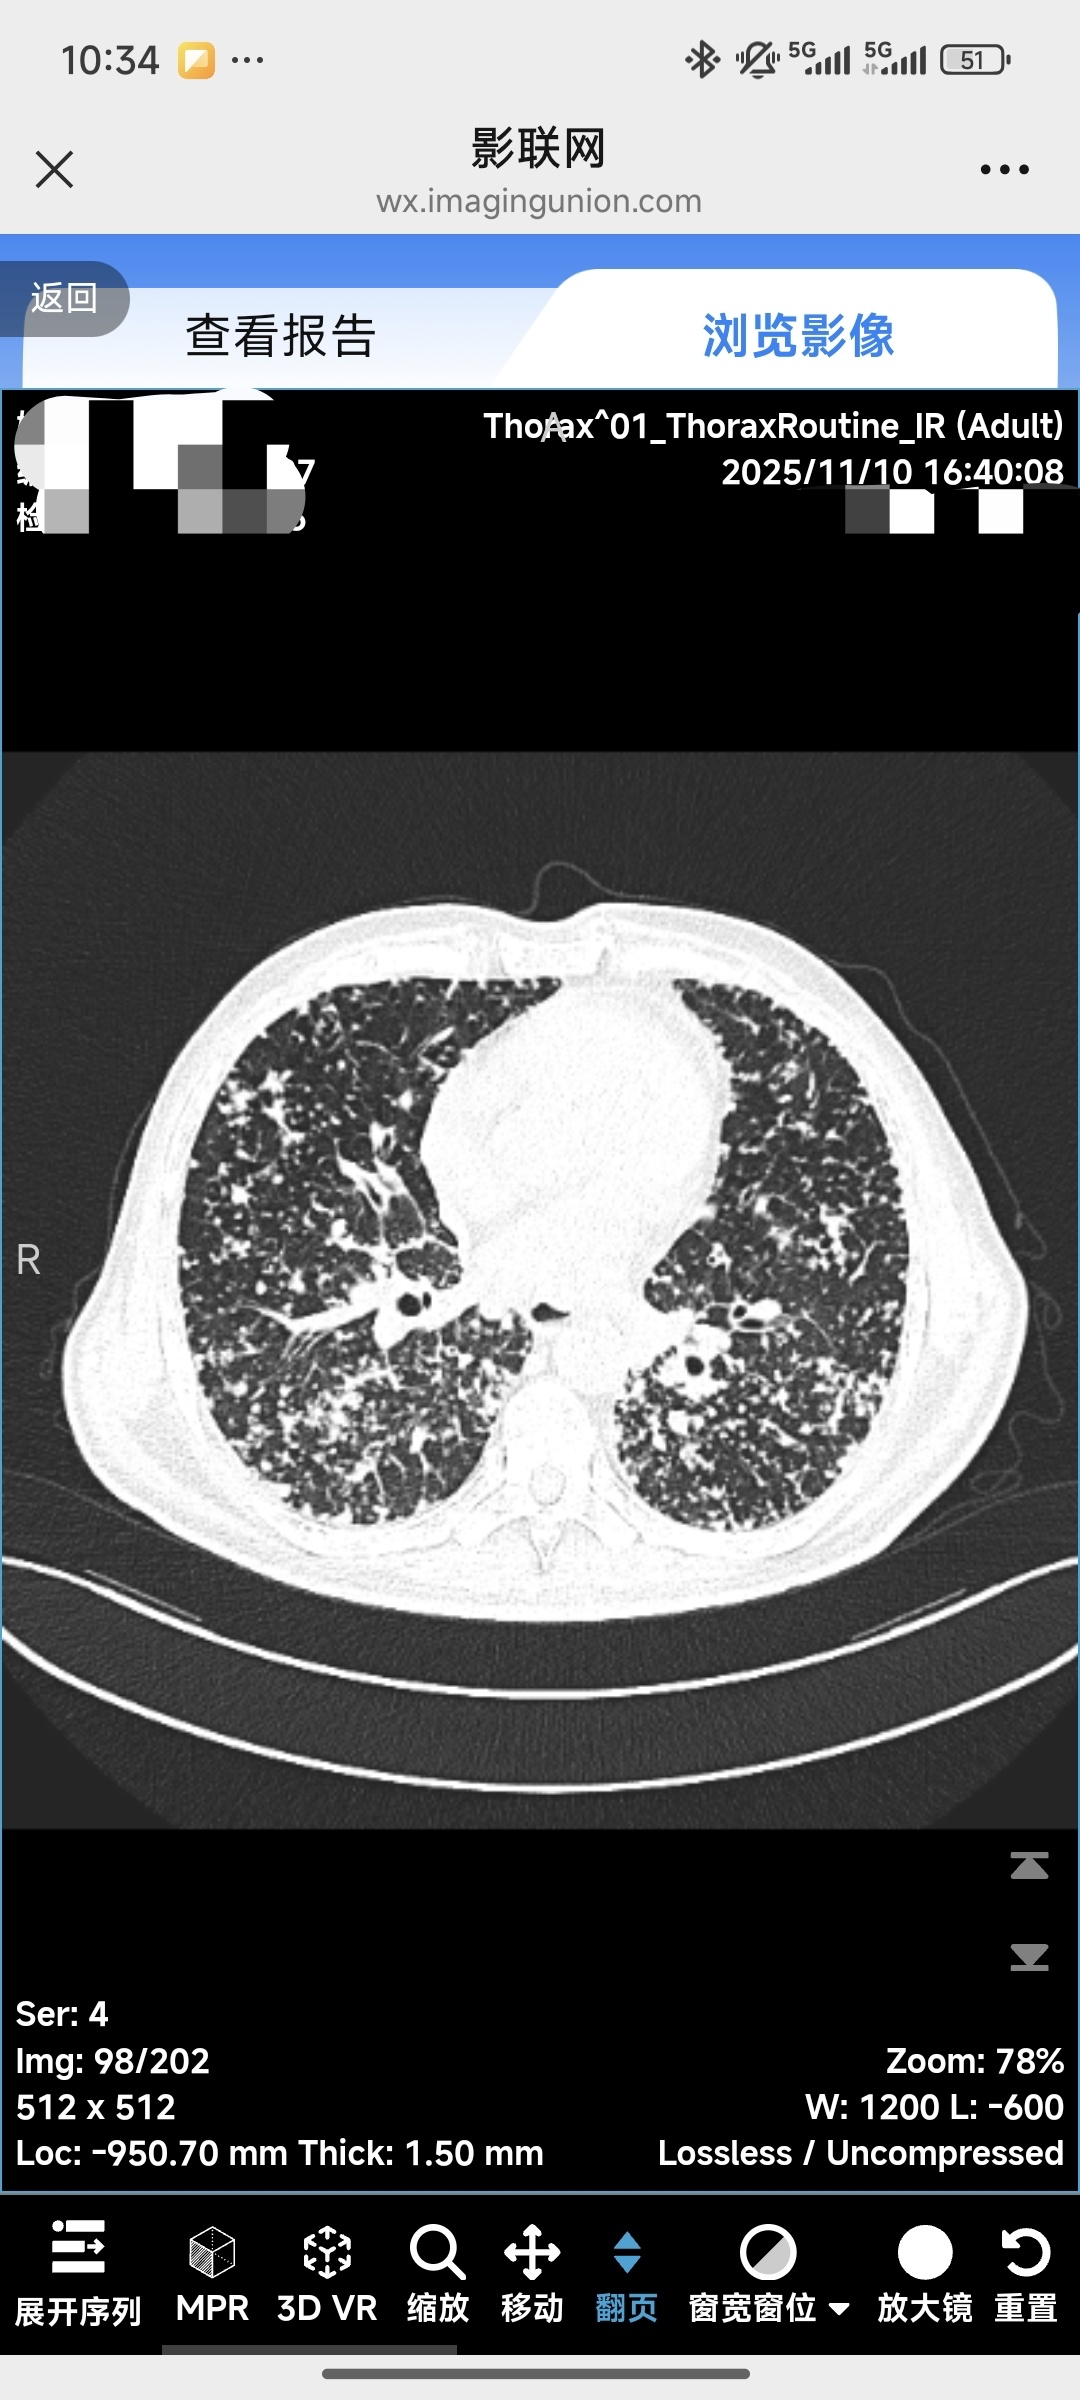

2025-11-10外院复查胸部CT。双肺较前进展